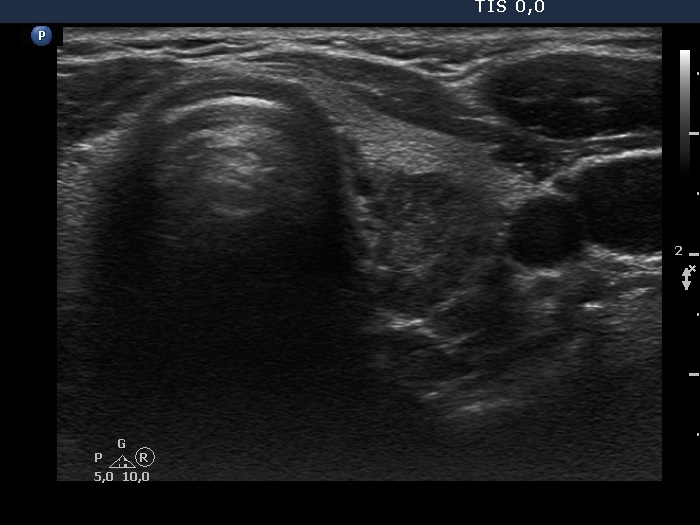

The borders of the nodule - case 2115 |

Clinical presentation: A 42-yr-old woman was referred for evaluation of a nodular goiter detected by chance on carotid Doppler examination.

Ultrasonography. The thyroid was echonormal. There was a mass in the dorsal part of the left lobe. The lesion presented parts with different echogenicities.

Comment. The issue is whether the lesion is composed of one or more nodules. In the former case it has lobulated margins, in the latter this is a non-pathological lobulation. Nonetheless, the question is only theoretical because the nodule requires cytological evaluation.